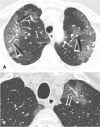

Purpose: COVID-19-related acute respiratory distress syndrome (ARDS) is characterized by the presence of signs of microvascular involvement at the CT scan, such as the vascular tree in bud (TIB) and the vascular enlargement pattern (VEP). Recent evidence suggests that TIB could be associated with an increased duration of invasive mechanical ventilation (IMV) and intensive care unit (ICU) stay. The primary objective of this study was to evaluate whether microvascular involvement signs could have a prognostic significance concerning liberation from IMV.

Results: A total of 139 patients affected by COVID-19 related ARDS were enrolled. After grouping based on TIB or VEP detection, we found no differences in terms of duration of IMV and mortality. Extension of VEP and TIB was significantly correlated with ground-glass opacities (GGOs) and crazy paving pattern extension. A parenchymal extent over 50% of GGO and crazy paving pattern was more frequently observed among non-survivors, while a VEP and TIB extent involving 3 or more lobes was significantly more frequent in non-responders to prone positioning.

Conclusions: The presence of early CT scan signs of microvascular involvement in COVID-19 patients does not appear to be associated with differences in duration of IMV and mortality. However, patients with a high extension of VEP and TIB may have a reduced oxygenation response to prone positioning.